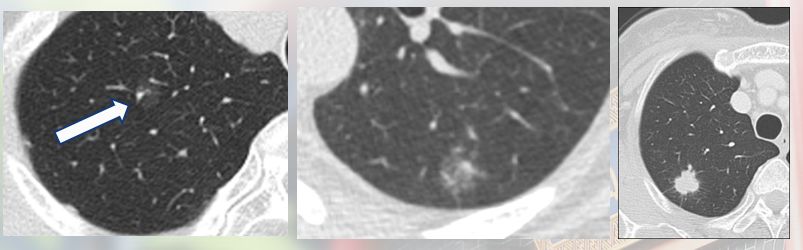

肺结节:影像(主要指CT)发现的直径<3cm的类圆形阴影。结节分为纯磨玻璃结节、混合密度结节和实性结节。

结节的3种密度类型

7mm磨玻璃结节,定期复查,20个月后CT发现结节长大,手术切除,病理证实为微浸润腺癌。因此,唐教授特意提醒大家,虽然磨玻璃结节50%以上为恶性,但也无需过分恐慌,因为其生长速度很慢,绝大多数小于7mm的磨玻璃结节均属很早期,可以定期复查,如果发现结节长大或密度增大,再手术切除。

磨玻璃结节,定期复查,5年均未见明显变化,继续随访。对于这种不生长的情况,专业称为“休眠”,休眠状态通常不需要手术治疗,患者可以带结节生活,因此,是否需要手术需要医生根据实际情况做专业判断。

8mm磨玻璃结节,定期随访,CT发现结节实性成分增多,手术切除,病理为腺癌。